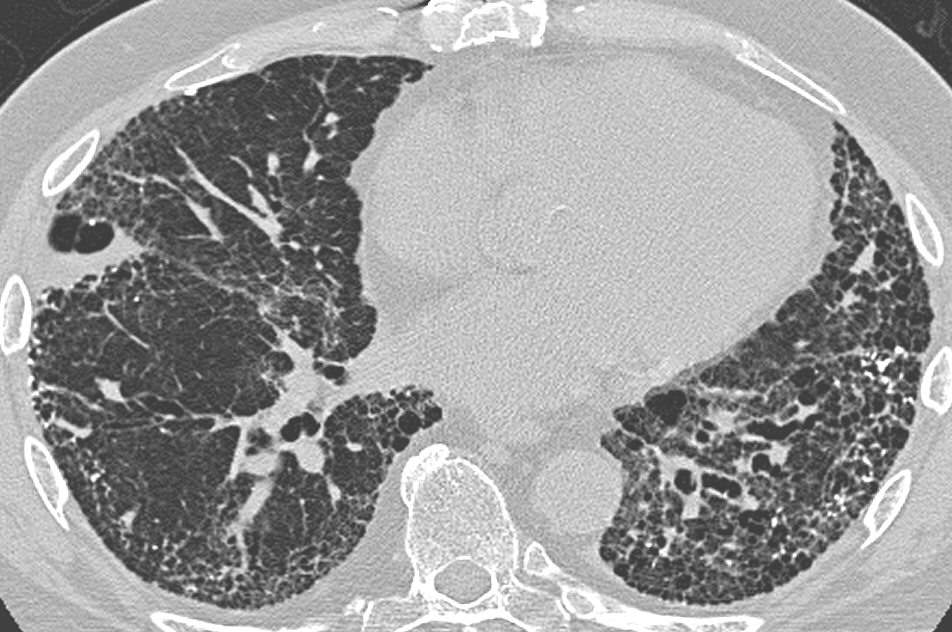

A 75-year-old man is evaluated in the emergency department for increasing shortness of breath for the last 8 months. He also complains of a dry cough for the last 6 months. Initially, his shortness of breath occurs with exertion, but now he feels it at rest as well. He has no other complaints. He has a sedentary lifestyle and had a hip replacement surgery recently. The past medical history is significant for hypertension for which he is taking lisinopril. The patient is a lifetime non-smoker. The blood pressure is 135/85 mm Hg, pulse rate is 85/min, and the temperature is 36.6°C (97.9°F). Physical examination reveals fine inspiratory crackles and digital clubbing. A chest X-ray reveals peripheral reticular opacities associated with traction bronchiectasis predominantly at the lung bases. The pulmonary function test results reveal a decreased FEV1, a decreased FVC, and a preserved FEV1/FVC ratio. High-resolution CT scan of the chest is shown. Which of the following is the most likely diagnosis?